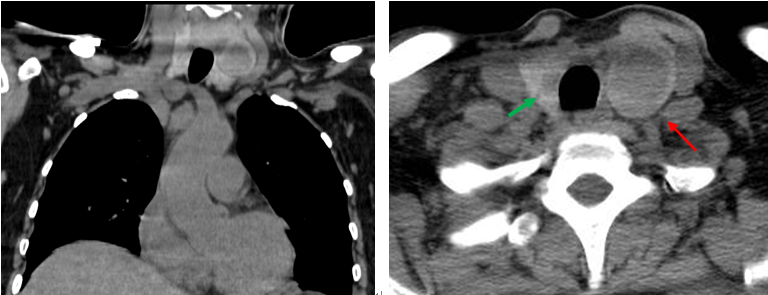

患者同期甲狀腺CT平掃檢查所見:

甲狀腺形態(tài)增大,雙葉見類圓形低密度影,大小分別為2.4×2.9cm(左,紅箭),0.7×1.1cm(右,綠箭)。